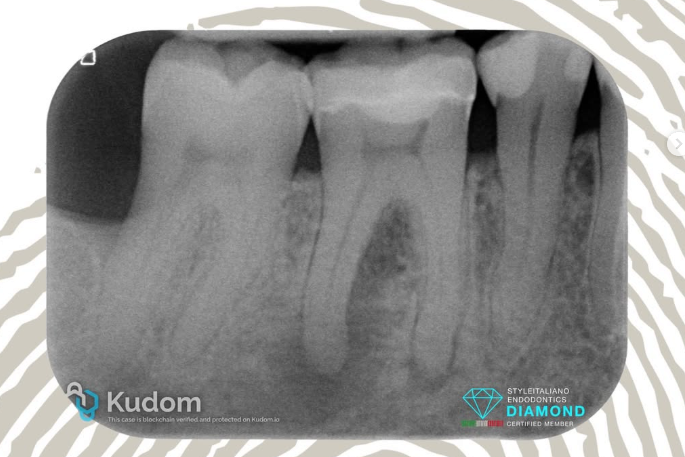

Retreatment 36 with lesion and Treatment of symptomatic 37 - 4 years follow-up.

Patient was referred for 2 problems: the tooth 36 was tender to percussion and palpation, the 37 presented the tipical signs of “Cracked tooth Syndrome” with no probing and favorable prognosis. Treatments were done in 2 visits. During the first visit teeth were shaped, cleaned and dressed with calcium hydroxide . During the second visit the canals were obturated using the Cold Hydraulic Condensation Technique, a single cone with CeraSeal bioceramic sealer. Nice recall sent by the referral Dentist after 4 years.